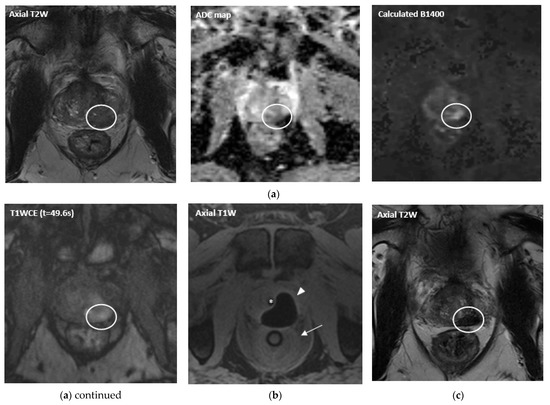

- Overduin, C.G.; Jenniskens, S.F.M.; Sedelaar, J.P.M.; Bomers, J.G.R.; Fütterer, J.J. Percutaneous MR-guided focal cryoablation for recurrent prostate cancer following radiation therapy: Retrospective analysis of iceball margins and outcomes. Eur. Radiol. 2017, 27, 4828–4836. [Google Scholar] [CrossRef]

- Bomers, J.G.; Overduin, C.G.; Jenniskens, S.F.; Cornel, E.B.; van Lin, E.N.; Sedelaar, J.M.; Fütterer, J.J. Focal Salvage MR Imaging–Guided Cryoablation for Localized Prostate Cancer Recurrence after Radiotherapy: 12-Month Follow-up. J. Vasc. Interv. Radiol. 2020, 31, 35–41. [Google Scholar] [CrossRef]